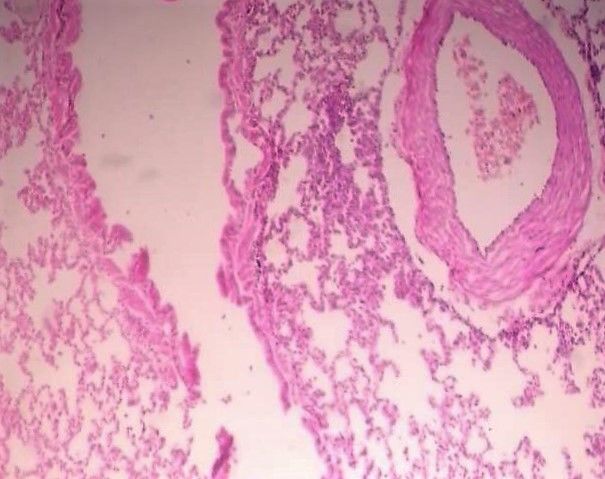

Question 14

Question

Label this image

Image:

8f9c7629-c4da-47ad-a96d-1da970040cdc (image/jpeg)

Answer

Adult Lung